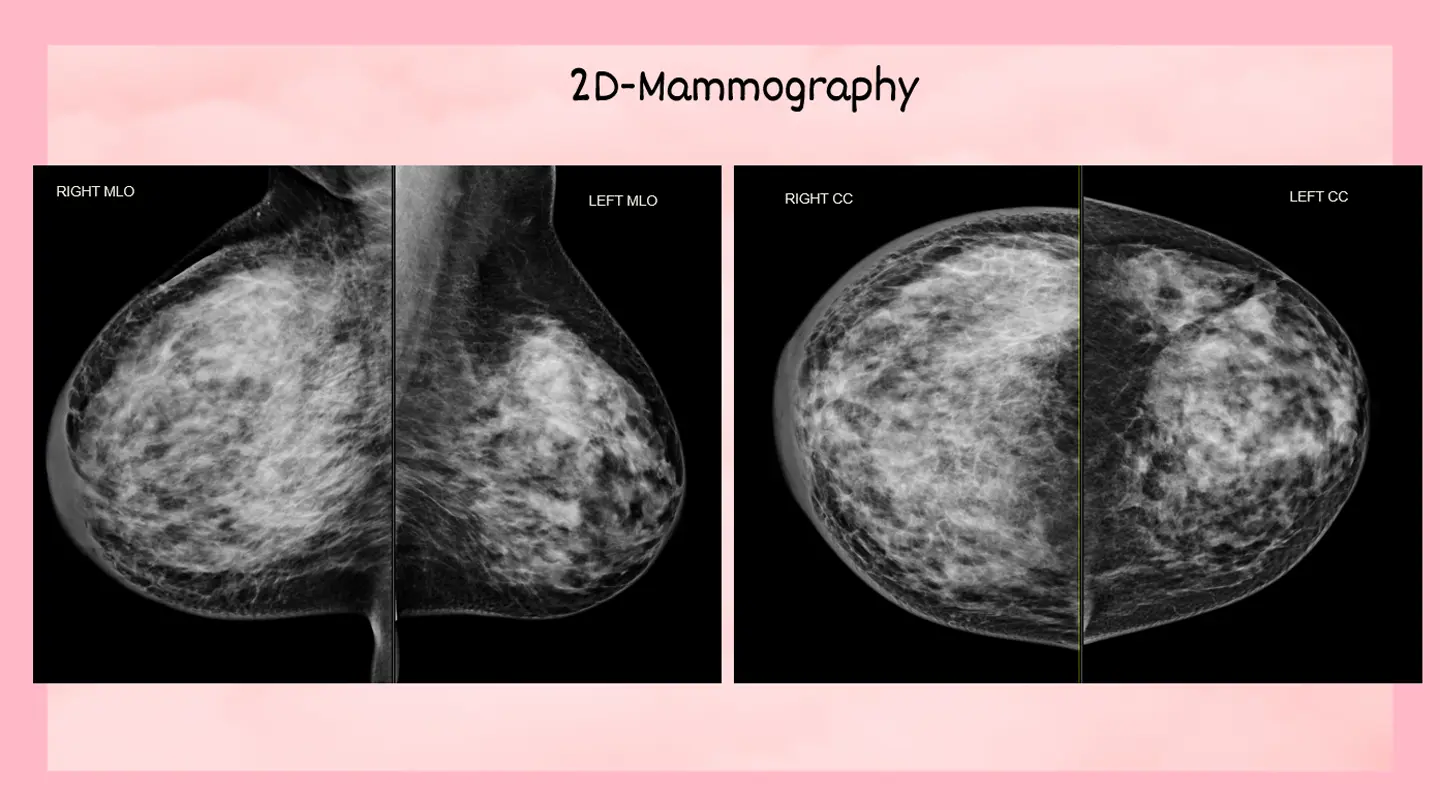

Mammography

April 2026